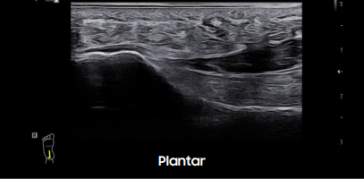

Galería de imágenes